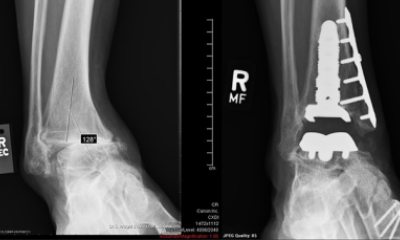

Tip on ankle replacement starts with an unlikely source After 43 years of hobbling on a mangled ankle, one man found the breakthrough that changed his life.